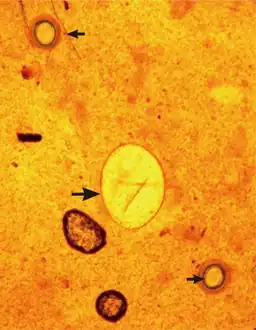

Micrograph of an unstained Echinostoma egg

Unstained Echinostoma egg.

An Echinostoma infection can be diagnosed by observing the parasite eggs in the faeces of an infected individual, under a microscope. Methods such as the Kato-Katz procedure can be used to do this.[3] The eggs typically have a yellow-brown appearance, and are ellipsoid in shape.[20] To confirm which species is causing the infection adult worms must be recovered from the infected individual, such as with anthelmintic treatment.[20]